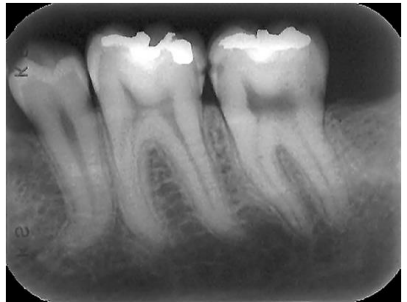

A auxiliar, antes de montar as radiografias intrabucais, deve preencher o nome do paciente, o número do prontuário e a data. Para realizar a montagem deve avaliar os pontos anatômicos e a anatomia dos dentes.

Considerando que o picote (saliência) do filme radiográfico está voltado para você, essa radiografia dos molares é do lado